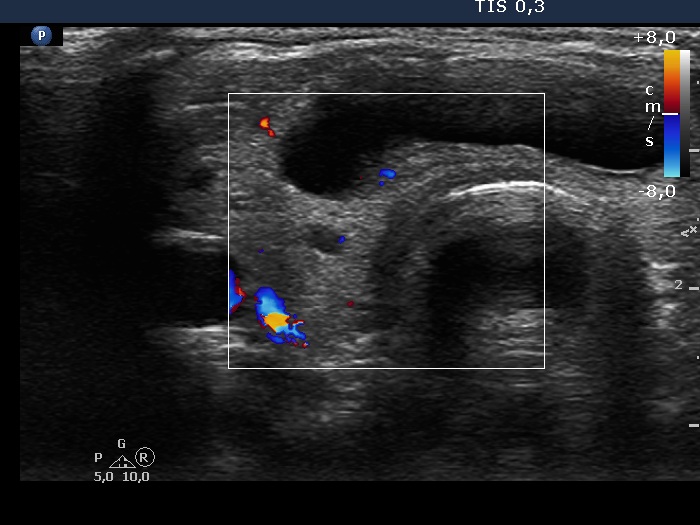

Intranodular hyperechogenic figures - case 1158 (ultrasonographic picture 7)

Isthmus, transverse scan, color Doppler mode. The vascularization is minimal.